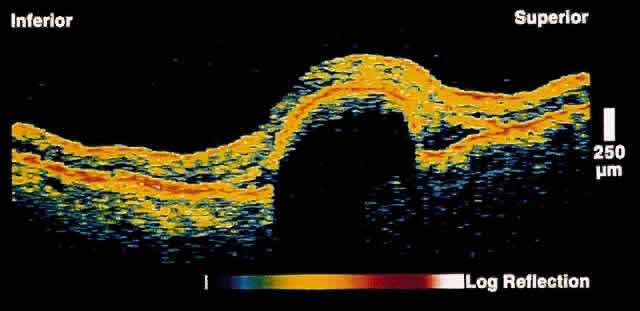

Retinal Detachment and Retinoschisis

Full-thickness retinal detachment can usually be distinguished from degenerative retinoschisis on the basis of clinical features alone. However, in some cases this is difficult; various ancillary tests such as laser photocoagulation, visual field evaluation, and B-scan ultrasonography can be helpful but are not always definitive. OCT is an objective and reliable method to distinguish the two entities.17 In retinoschisis, OCT images show splitting of the neurosensory retina consistent with the known histopathology of a separation at the outer plexiform layer (Fig. 14). Retinal detachment presents as a separation of full-thickness neural retina from the underlying RPE band (Fig. 15). Although lesions anterior to the equator cannot be imaged by OCT, most lesions that are posterior to the equator, or that have a component posterior to the equator, can be effectively imaged.

Fig. 14. OCT image through peripheral retinal elevation suspected to be retinoschisis versus retinal detachment. This image shows a splitting of the neurosensory retina consistent with retinoschisis.

Fig. 15. OCT image through peripheral retinal elevation suspected to be retinoschisis versus retinal detachment. This image shows a full-thickness detachment of the neurosensory retina consistent with a retinal detachment. In contrast to retinoschisis, splitting of the neurosensory retina is not present.